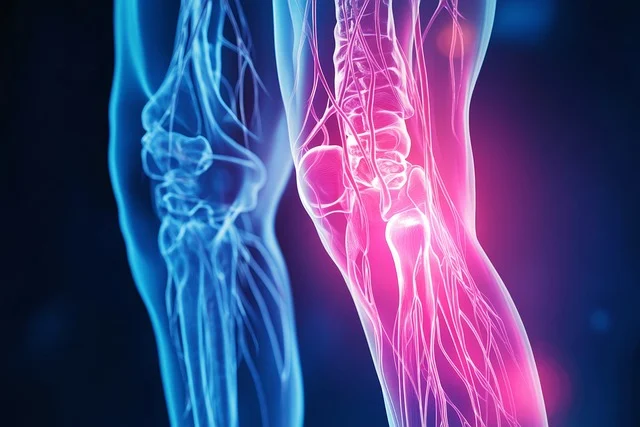

⦁ 관절에 연골은 관절이 받는 하중을 흡수하고 움직임을 부드럽게 만들어주는 역할을 합니다.

⦁ 관절의 사용향이 많아지면 연골이 마모되고 손상이 되면서 관절을 보호해 주지 못하기 때문에 통

증이 발생하게 됩니다.